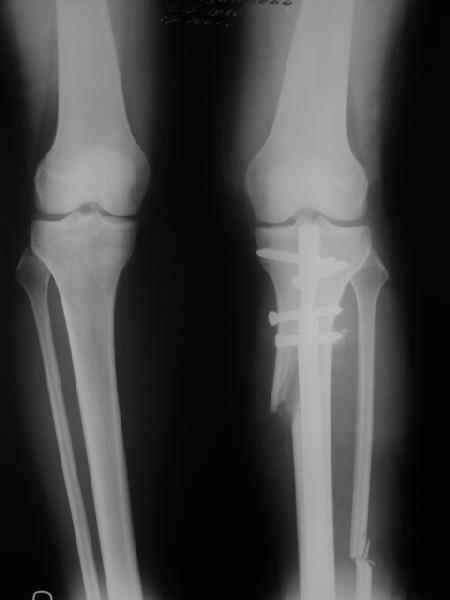

Re: Деформация голеней

Yesterday i performed correction of one leg (the plan to make both in one session was cancelled because of some external reasons). Suggestions of Nuno Lopes were most close to my view. A small wire distractor was used intraoperatively. Derotation ~6-7 degrees was performed also. CT scans evaluating rotation will be available only

tomorrow. No problem to change rotation of the operated limb in the moment of the second surgery. Comments/critics are welcome.

Can the attached result be analyzed by the software?